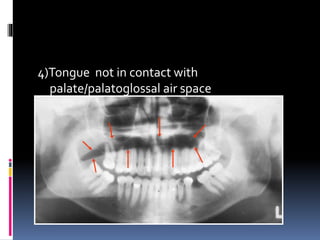

4)Tongue not in contact with

palate/palatoglossal air space